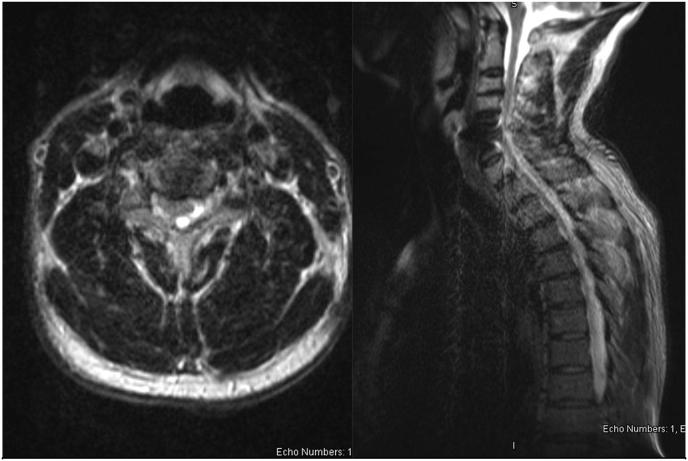

We present a 49-year-old robust male who underwent a temporary cervical SCS trial and was diagnosed with epidural abscess on the day 9 when the leads were pulled. The trial phase was complicated by immediate and prolonged post procedure pain. The diagnosis of epidural abscess was made soon after clinical presentation with no neurological deficits or escalation in pain but new onset fever. He made a complete recovery after extensive laminectomy and antibiotic treatment.

我们报告一名49岁的健壮男性,他接受了临时颈椎脊髓刺激试验,在拔除电极的第9天被诊断为硬膜外脓肿。试验阶段因术后立即出现且持续存在的疼痛而变得复杂。在出现临床表现后不久即诊断出硬膜外脓肿,当时没有神经功能缺损或疼痛加剧,但出现了新的发热症状。经过广泛的椎板切除和抗生素治疗后,他完全康复。